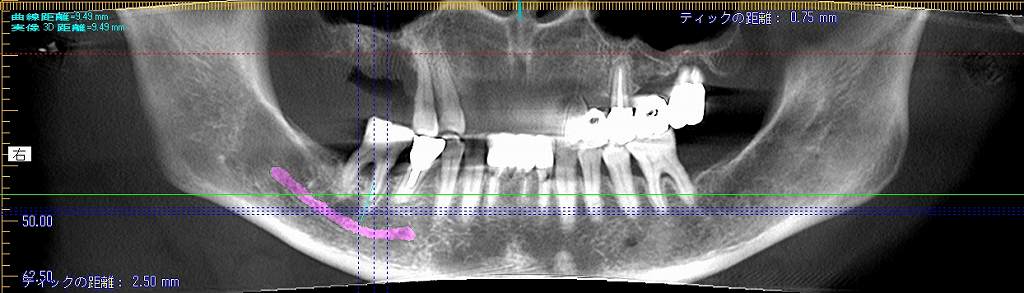

術前のパノラマになります

術前と術後のパノラマになります